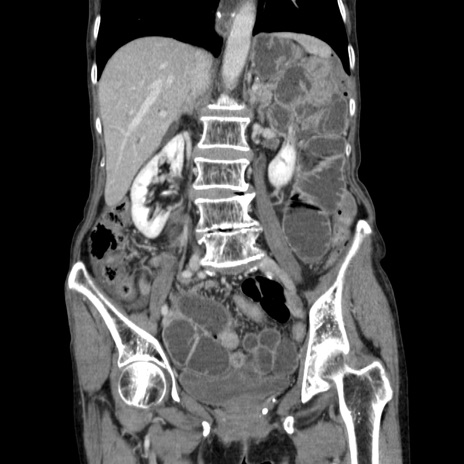

横断像

【症例】80歳代女性

【主訴】胸のつかえ感

【現病歴】約9時間前に食後から胸のつかえた感じあり、嘔吐あり、来院。

【既往歴】胃癌(全摘)、胆摘、虫垂炎

【身体所見】心窩部に圧痛あり、反跳痛なし。

【データ】WBC 5700、CRP 0.05